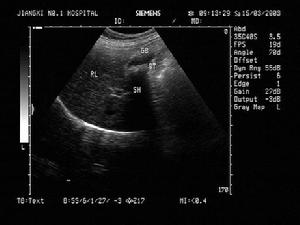

常在CT檢查中表現為膽囊內透聲差,充滿密集點狀強回聲團,膽囊腫大,壁增厚。